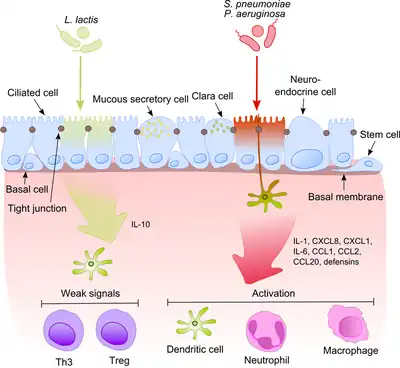

a)Image reveals tuberculosis asterisk b) CT scan of the chest shows tuberculosis with cavitation asterisk Commensals vs pathogenic bacteria in COPD

Commensals vs pathogenic bacteria in COPD An abscess caused by opportunistic S. aureus bacteria.